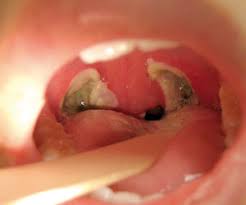

يُعد التهاب اللوزتين التهابًا يصيب اللوزتين، وهما جزآن لينان بيضاويا الشكل من الأنسجة والتي توجد في نهاية الحلق حيث توجد لوزة في كل جانب. ما هي اعراض التهاب اللوزتين عند الاطفال؟ تتشكل أنسجة بيضاء الشكل في مؤخرة الحلق عند إصابة الطفل بإلتهاب اللوزتين بسبب دخول جراثيم أو ميكروبات إلى الجسم عن طريق الفم. ان تضخم اللوز في بعض الاحيان بشكل كبير مع وجود الالتهاب او بدونه قد يسبب الشخير عند الاطفال، فاذا حدثت حالات اختناق جراء تضخم اللوز واستدعت الضرورة فيمكن ازالتها عند عمر ستة شهور، ومن طرق ازالتها يتمثل العلاج في مراجعة الطبيب المختص ليعطي الطفل الدواء اللازم كالمضادات الحيويّة التي تُخفف شدة الالتهاب والتضخم، إلى جانب الأخذ بالعادات الصحيّة السليمة أثناء فترة العلاج كالنوم والراحة، وشرب كميّة كافية من السوائل. تظهر بعض الأعراض على الطفل بعد التعرض لتضخم اللوز ومنها

حصى اللوزتين ويكيبيديا

حصى اللوزتين ويكيبيديا from upload.wikimedia.org

ملاحظة التهاب اللوزتين باستخدام خافض اللسان وملاحظة تكون تقيحات. تتم معالجتها حالياً بجرعة واحدة من الستيروئيدات عند كل التهاب. وجع الحلق، وقيل دم يهيج في حلق الإنسان، وتتأذى منه اللحمتان اللتان. التهاب اللوزتين هو مرض من الأمراض الشائعة والمنتشرة بشكل كبير وخصوصا عند الأطفال. يسبب التهاب الأذن الوسطى آلاما كبيرة عند الأطفال. • ما هي أسباب انسداد الأنف عند الأطفال: انسداد الأنف المزمن والذي يؤثر على نوم الطفل غالبا ما يكون بسبب تضخم اللحمية البلعومية وقد يصاحبه تضخم في اللوزتين ايضاً. يُساهم تضخم اللوزتين في حدوث تضيّق في المسالك الهوائية، مما يزيد من فرص الإصابة بالشخير وانقطاع النفس أثناء النوم. إيقاف التهاب اللوزتين قبل حدوثه. أسباب تضخم اللوزتين عند الأطفال. .اللوزتين عند الاطفال عمر سنتين بالاعشاب وصفة فعاله لعلاج تضخم والتهاب اللوزتين عند الاطفال بمكون واحد من مطبخك كيف نمنع مع الدكتور الفايد بخصوص النظام الغذائي للطفل التهاب اللوزتين عند الأطفال. أهم المعلومات عن التهاب اللوزتين. التهاب اللوزتين عند الاطفال يصاحبه تضخم الناميات الانفية او ما يسمي باللحمية ، والتي هي ايضا تتكون من نسيج ليمفاوي شبيه بنسيج اللوزتين ، وتضخمها سيحدث ضغطا علي الفتحتين السفليتين لقناة استاكيوس وربما انغلاقهما ، والذي سيؤدي حتميا الي تجمع.